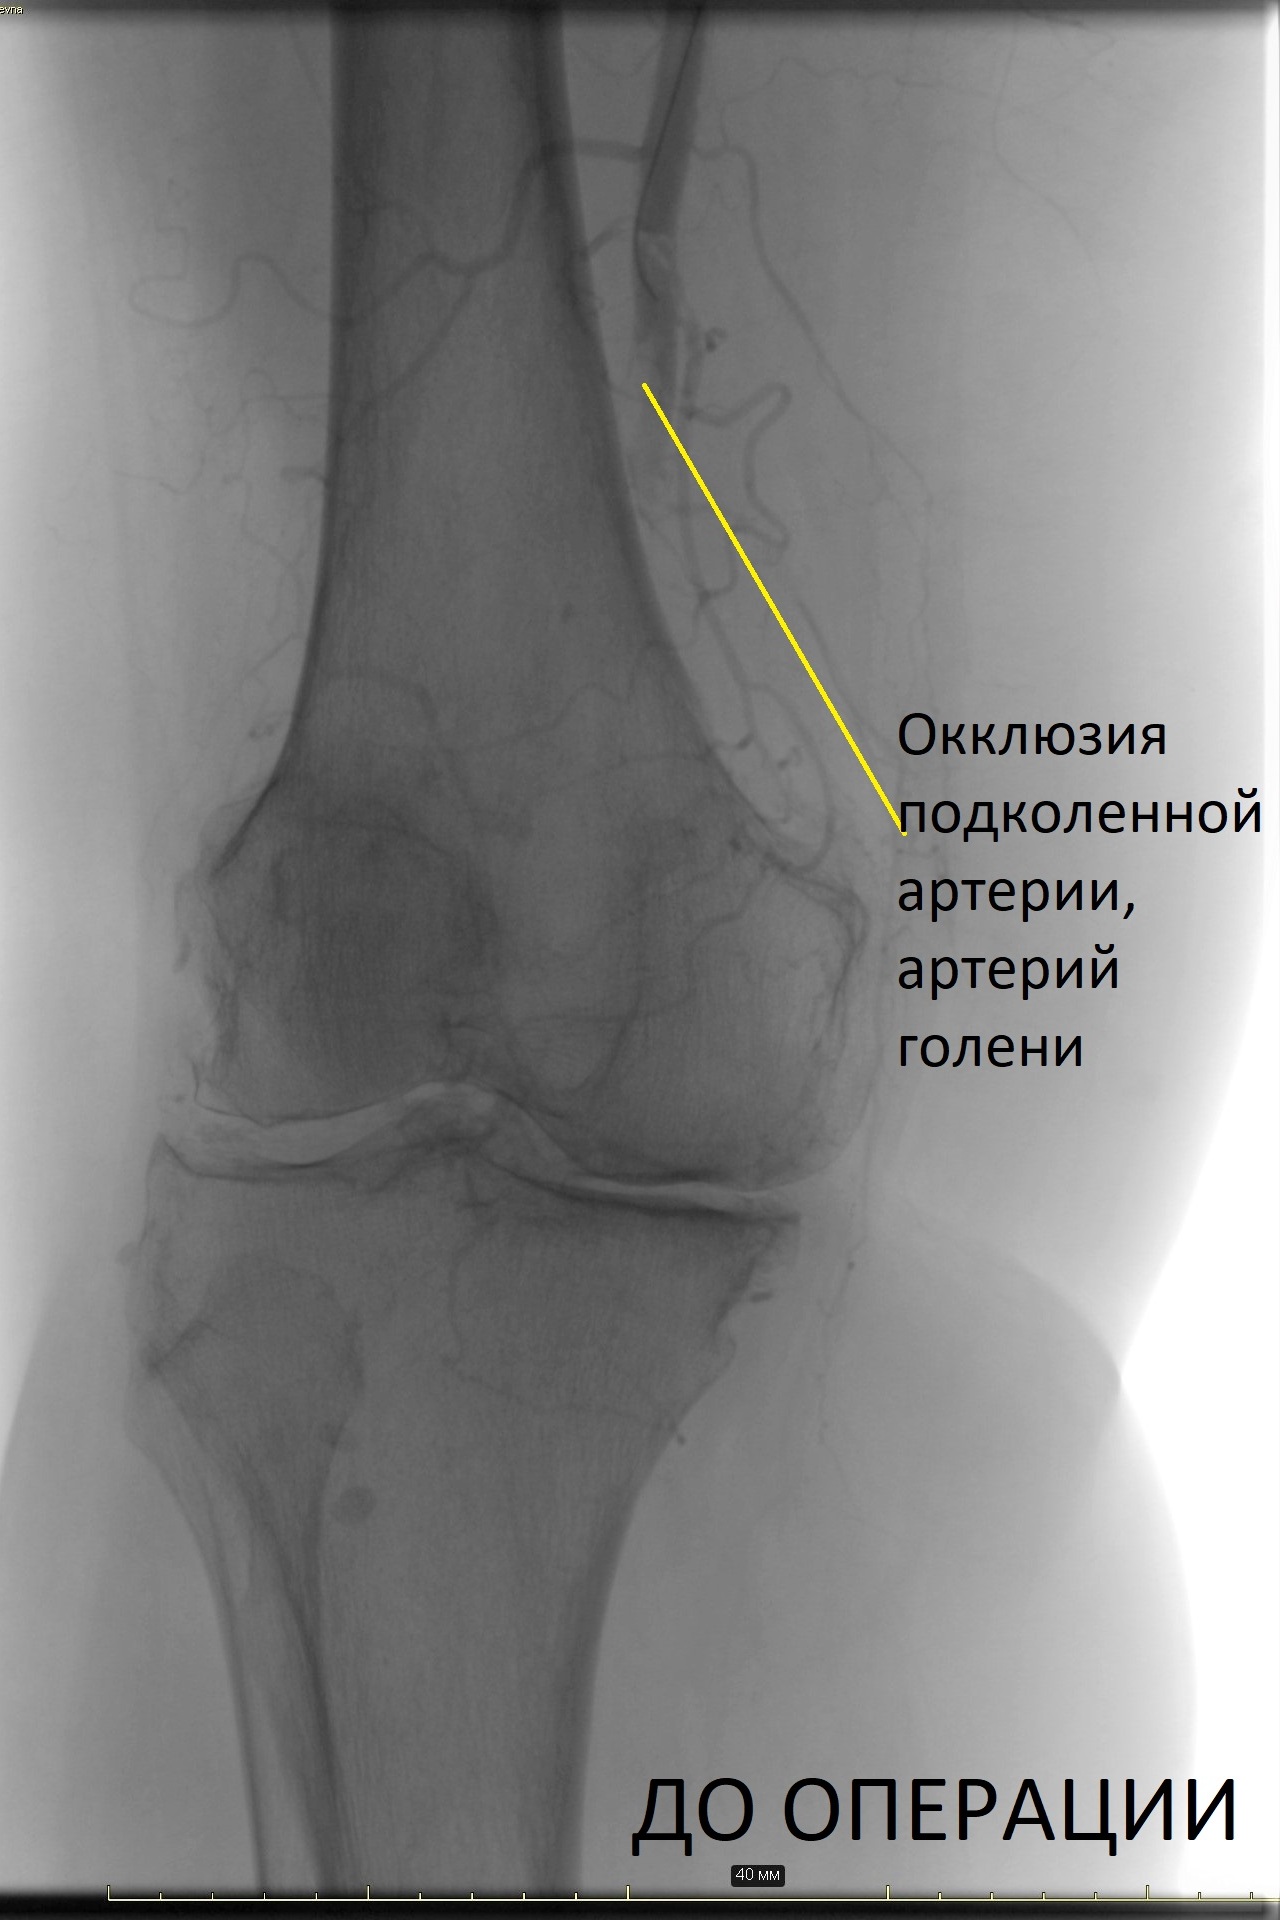

Центр Алмазова является уникальным учреждением, в котором в повседневную клиническую практику интегрированы мультидисциплинарный подход и персонифицированная медицина, основанные на сотрудничестве и взаимодействии медицинских специалистов смежных дисциплин. Уже 6 месяцев на базе клиники сосудистой хирургии учреждения успешно работает команда профессионалов, оказывающая высокотехнологичную помощь больным с диабетической стопой с применением в лечебном процессе инновационных малоинвазивных и гибридных технологий, в том числе эндоваскулярной реваскуляризации артериального русла.

Благодаря ежедневной слаженной работе команды сосудистых хирургов, кардиологов, эндокринологов и травматолога-ортопеда, удалось избежать больших ампутаций, а значит, и серьезной инвалидизации этих пациентов, добиться заживления трофических язв, восстановления двигательных функций. Все больные смогли вернуться к привычному образу жизни. После выписки они находятся под динамическим наблюдением специалистов учреждения.

Залогом успеха в лечении этой категории больных является выстраивание индивидуальной стратегии, включающей такие этапы, как реваскуляризация артериального русла, коррекция сахарного диабета, рациональная антибактериальная терапия, костно-пластическая реконструкция, а также лечение других осложнений сахарного диабета. Только при соблюдении всех этих принципов удается добиться результата, к которому стремится каждый специалист большой команды Центра Алмазова.